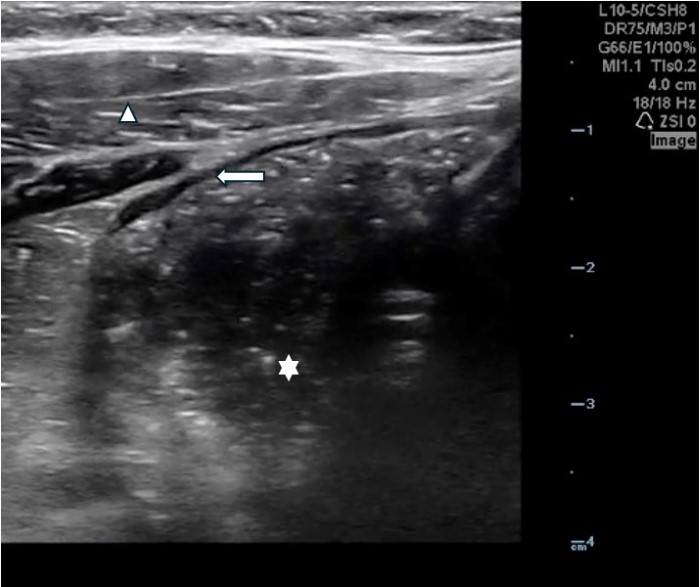

The linear probe is placed in the RLQ in the transverse position with indicator to the patient’s right. Identify the psoas muscle and iliac vessels lying medial. Once these structures are visualized, slide lateral and look superficially to identify the cecum. (Figures 1a,1b 1) Use graded compression-progressive increase and decrease of pressure to move any gas out of view. Keeping the lateral edge of the abdominal cavity in view (Figure 2), the ultrasound probe should slide cranial in traverse plane, visualizing the ascending colon until the hepatic flexure.  In this location, the colon turns just medial to the liver with the kidney deep in the view. (Figure 3) This is the most common location to identify ileocolic intussusception. If no tissue mass is identified, the probe should be turned to the sagittal plane with indicator toward the head (to keep the colon visualized in the transverse view) and moved across the transverse colon continuing to use graded compression to look for a tissue mass consistent with intussusception. Once at the splenic flexure (Figure 4), the probe should be transitioned back to the transverse orientation to interrogate the descending colon.

10-2024 Article7-2.jpgFigure 2. Lateral border of right abdomen maintained in view with “starry night” appearing stool in colon (white star), transverse abdominus muscles (triangle) and border of the peritoneal cavity (white arrow)